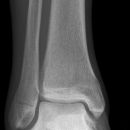

Sprunggelenk

Weber A

Weber B

Weber C + dorsales Volkmann

Trimalleoläre

Vorderes Volkmann + lat. Talusschulter